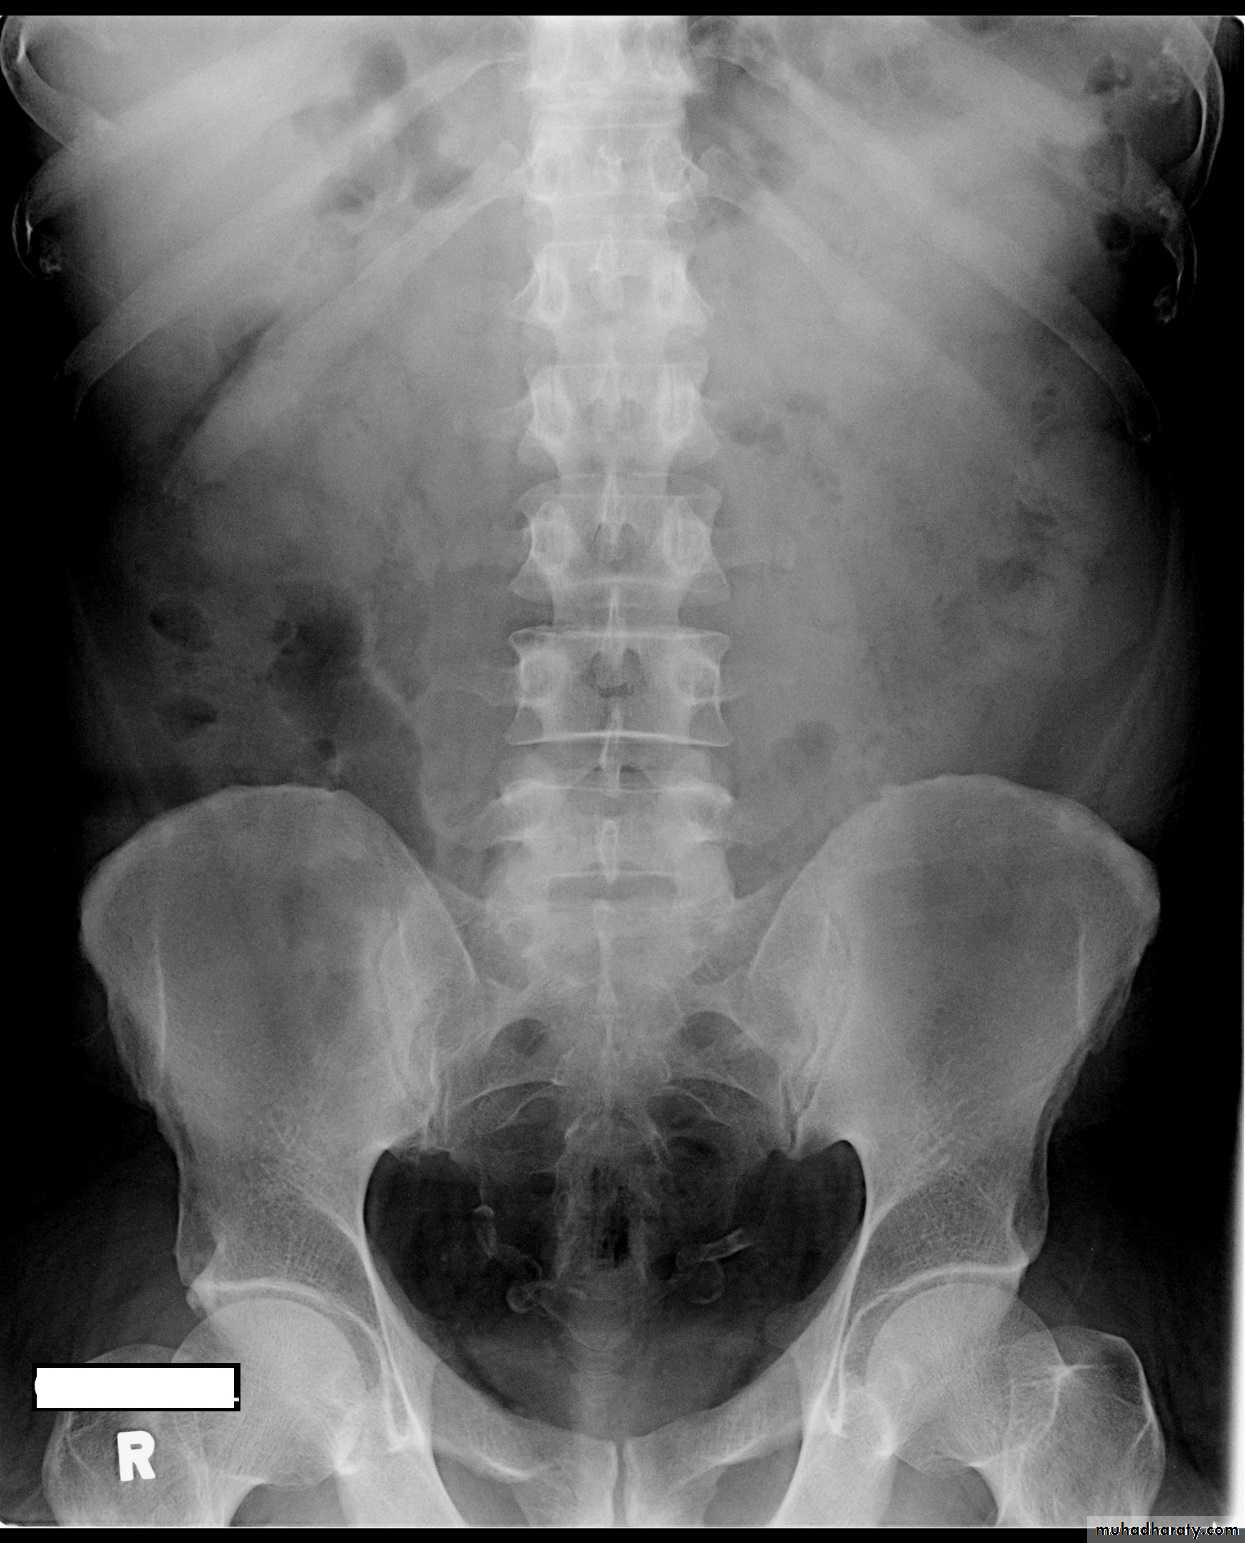

Congenital intrinsic pelviureteric junction (PUJ) obstruction

In this disorder, peristalsis is not transmitted across the pelviureteric junction.Childern and young adult

Dilatation of the pelvis and calices, with an abrupt change in caliber at the pelviureteric junction

the ureter is either narrow or normal in size.